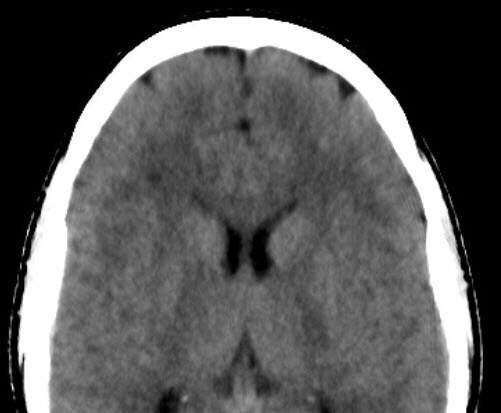

Sydney Xray Bondi Junction “IMR was capable of demonstrating the multiple lesions in the brain that was confirmed on the MRI scan. Nice improvement in image quality and compares well with MR.”

Australia

Dr. Sesel & Team